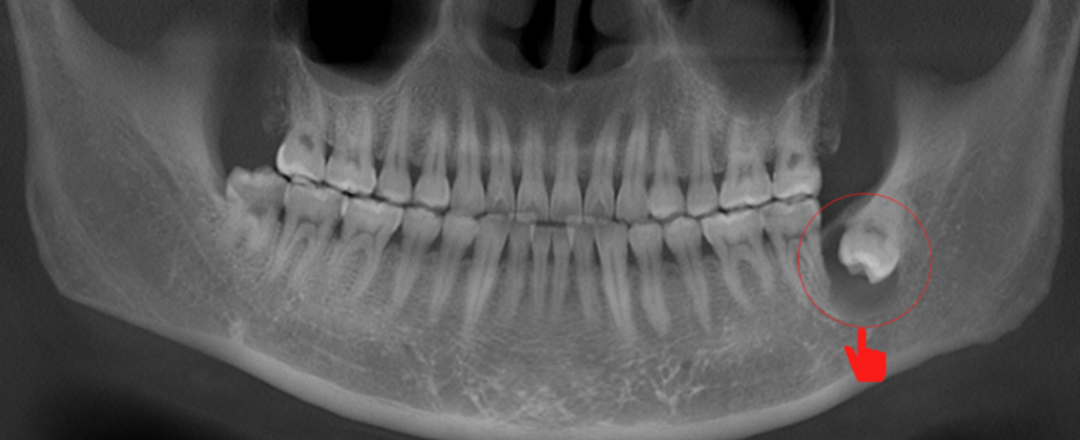

34岁男患者,下颌骨发育性囊肿

(李延超医生提供)

入院前3个月,下前牙不时发生疼痛,半个月前感觉到黏膜鼓包,嘴里有咸咸的味道(其实是囊肿内的液体物质渗出),到某口腔诊所拍牙片,看到下颌骨不明阴影。

转入我院口腔颌面外科,经影像学检查发现巨大囊肿,侵犯了多达6~7个牙位,造成牙齿疼痛,诊断为“下颌骨囊肿”。为了防止复发,需要先做根管治疗,再进行囊肿切除术。